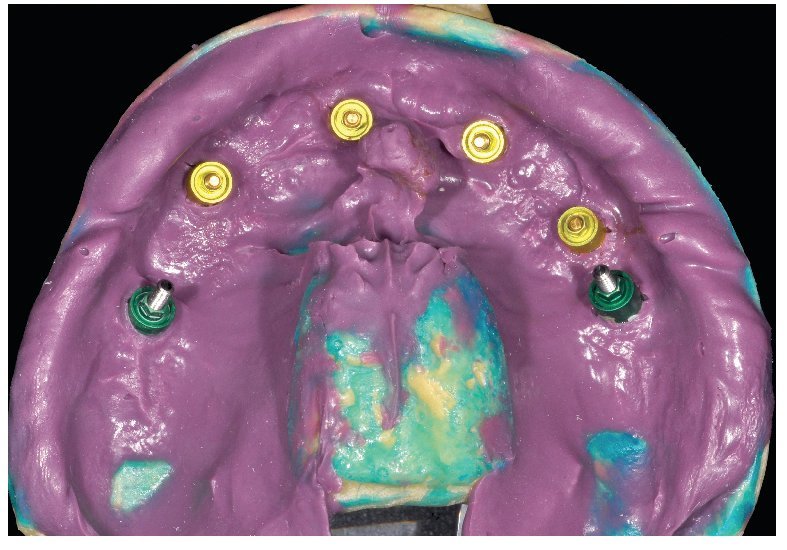

Fig. 76. La toma de impresión definitiva en el maxilar superior tiene lugar a la altura del hombro del implante.

Fig. 78. Vista detallada de la impresión del maxilar superior.